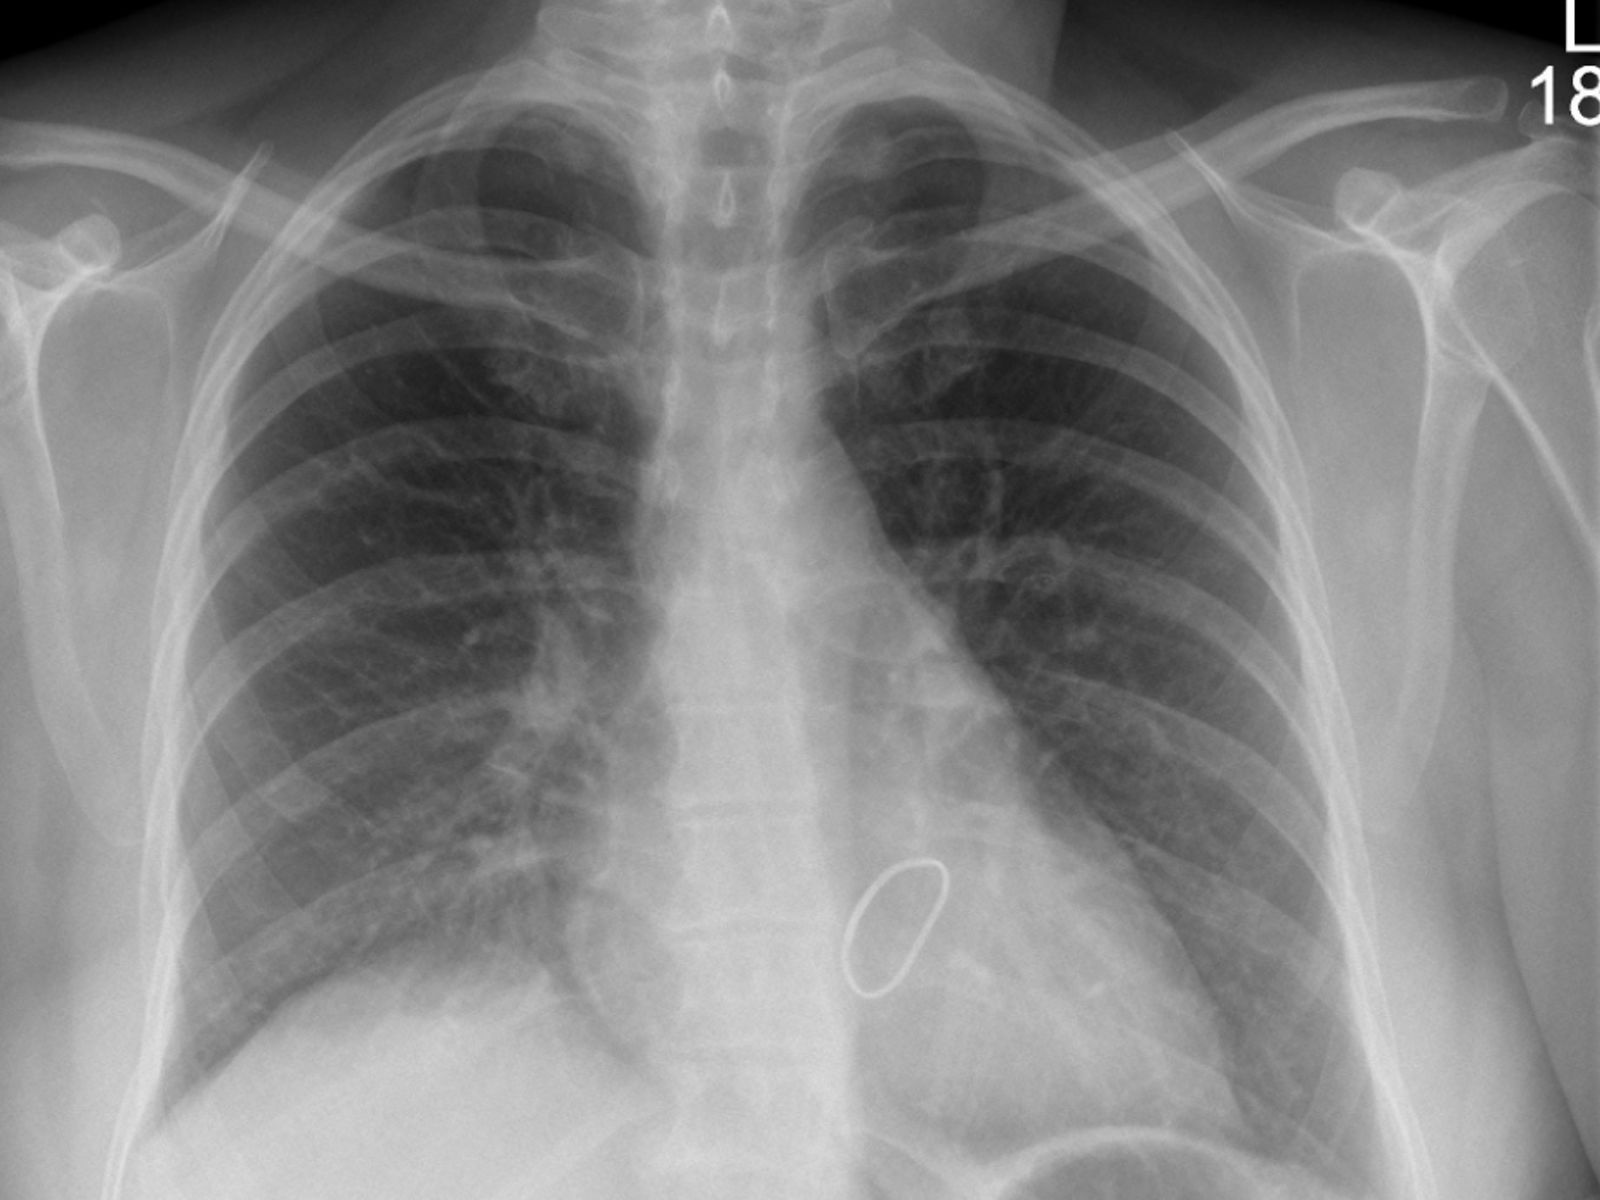

Was ist eine Zwerchfellparese?

Das Zwerchfell ist der wichtigste Atemmuskel. Wenn es teilweise oder vollständig gelähmt ist (Parese), kann es nicht mehr richtig arbeiten. Das führt in manchen Fällen zu Atemproblemen.

Welche Symptome treten auf?

Nicht jeder Patient hat Beschwerden. Etwa 50 % der Betroffenen merken nichts und brauchen daher keine Behandlung. Wenn Symptome auftreten, gehören dazu:

• Luftnot bei Belastung

• Atemprobleme im Liegen

• Luftnot im Wasser

Wie wird die Diagnose gestellt?

Um die Zwerchfellparese zu erkennen, führen Ärzte verschiedene Untersuchungen durch:

• Lungenfunktionstest

• Computertomografie (CT) des Brustkorbs

• Magnetresonanztomografie (MRT) des Halses

• Ultraschall des Zwerchfells